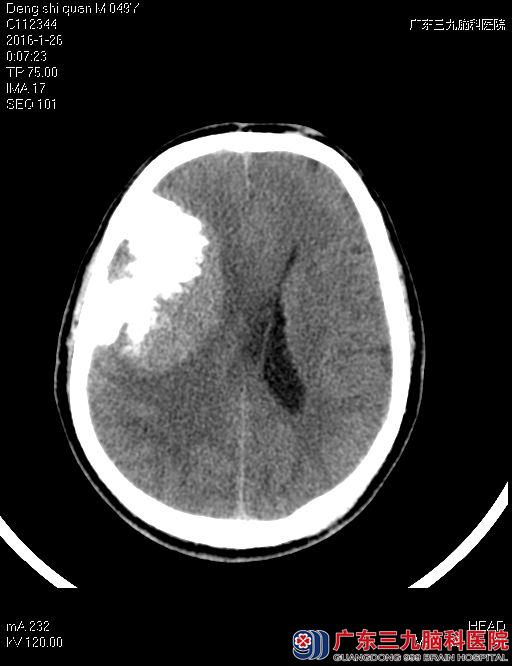

术后邓先生复查MRI,提示:右侧额颞部原病灶已全切除。医生继续给予其对症治疗。11天后,邓先生完全康复出院。

术后图片

该患者肿瘤巨大,占位效应明显,血供极其丰富,右侧轻度大脑镰下疝形成。如直接开颅手术切除,出血量多,创伤大,风险高,术后恢复时间长,出现并发症可能性大。因此,如何以最少的出血和创伤全部切除肿瘤是手术的难点。开颅手术前行全脑血管造影检查发现,肿瘤由颅内外血管联合供血,经微导管超选供血动脉行血管内栓塞治疗,将肿瘤供血动脉部分栓塞后可大大降低手术过程中大出血风险。开颅术中细心分离与正常脑组织粘连肿瘤,仔细分离肿瘤压迫的正常血管及神经,最后完整切除肿瘤组织。术后病理诊断为:右侧额颞部巨大脑膜瘤(过渡型WHO Ⅰ级),脑膜瘤为良性肿瘤,全切肿瘤后复发几率极低,治疗效果显著,手术出血少,术后给予积极的抗感染、营养神经、改善微循环等治疗后,患者短时间内完全康复出院,恢复正常生活及工作。